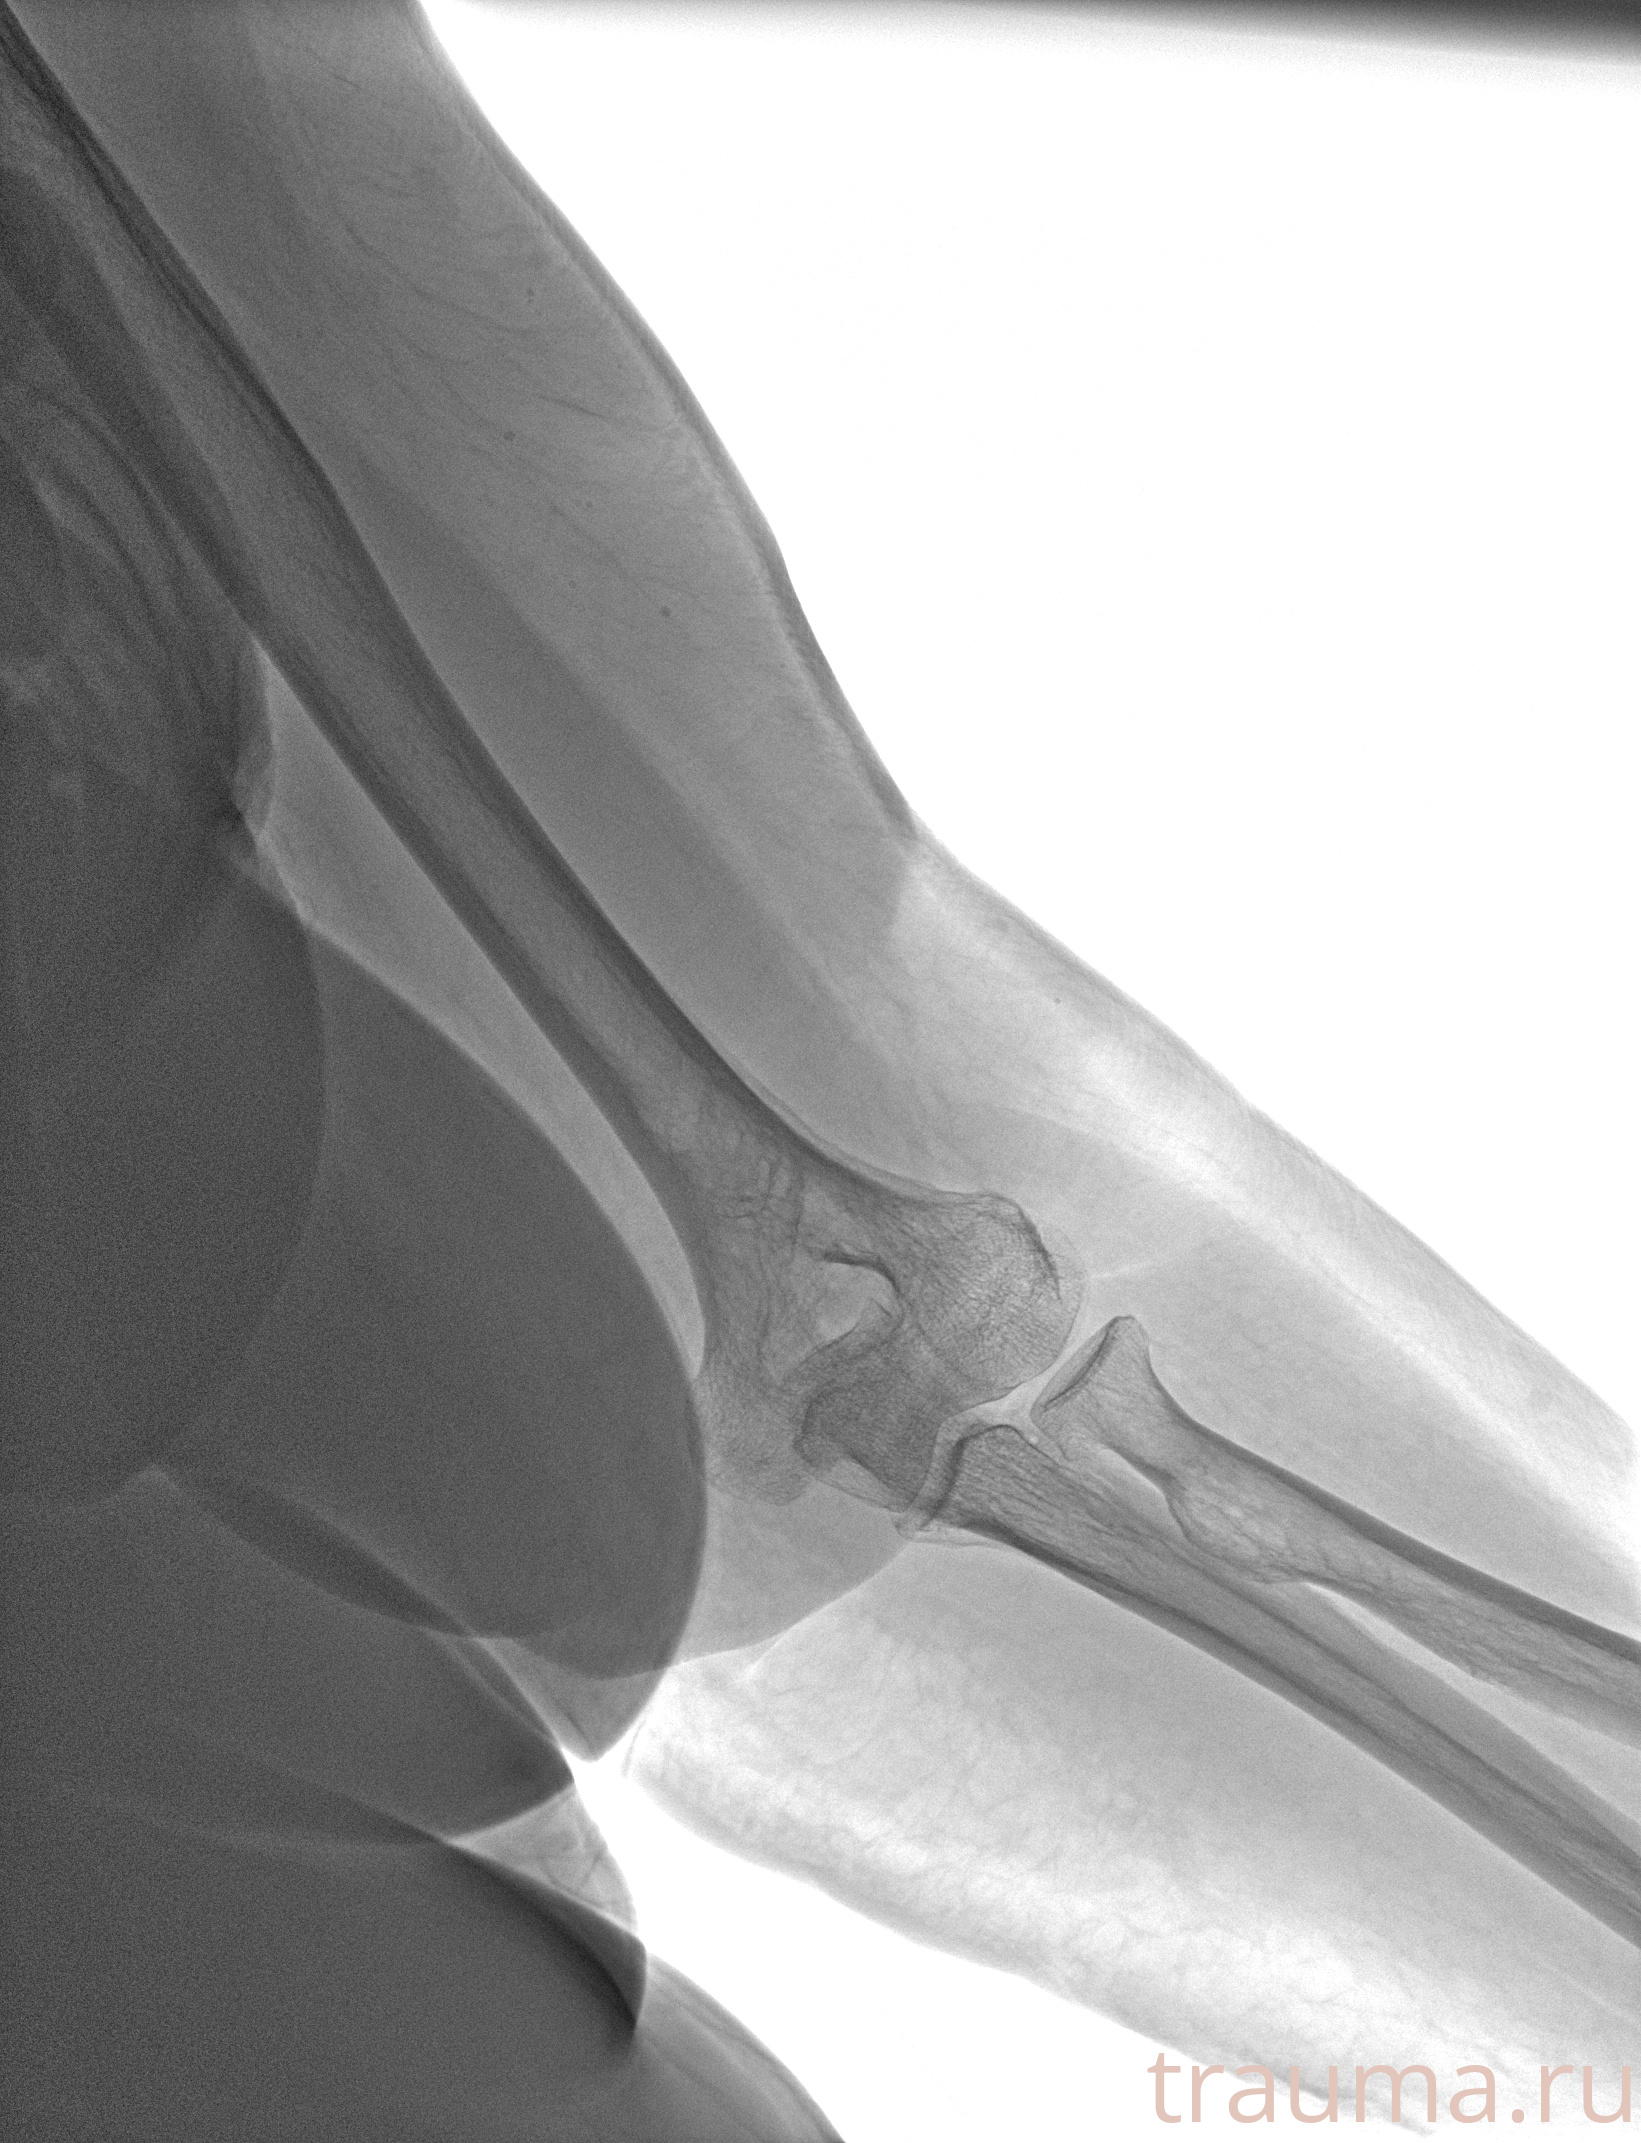

Рентген на дому: по вашему адресу приезжает врач-рентгенолог, травматолог-ортопед с мобильным рентгеновским аппаратом, проводит диагностику травмы или заболевания, делает необходимые рентгенограммы, дает рекомендации по дальнейшему лечению. Получить качественные снимки в домашних условиях возможно благодаря уникальной методике, разработанной МосРентген Центром для института  Склифосовского

при переломе шейки бедра и пневмонии от компании МосРентген Центр - партнера Института имени Склифосовского